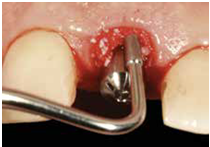

患者之後於96/11/08在右下第一小臼齒與植體間有膿胞產生,並於97/02/21確認右下第一小臼齒有根裂的情形,因此在97/02/29拔除此牙;經過將近半年後,於97/09/23放置一顆植體於此位置

98/01/08經過三個半月做右下第一小臼齒的二階暴露,發覺鄰牙的植體高度竟已掉下來

980305幫患者補角化牙齦並翻開清除發炎組織,期待能阻止繼續骨破壞